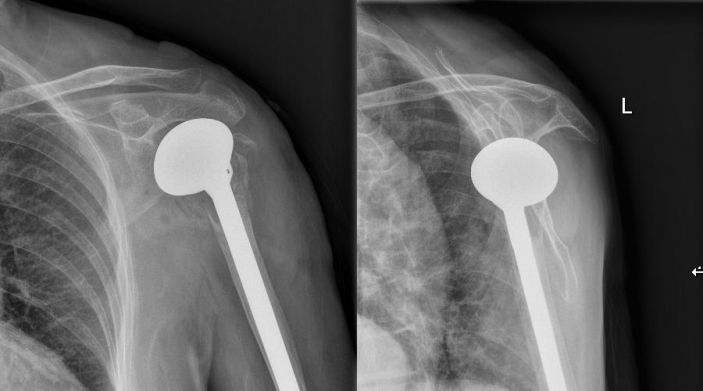

吳主任根據CT+三維重建先行拟訂詳細的手術方案。9月4日在經過充分的術前準備後,老太太被送進了層流淨化手術室,行左側人工肱骨頭置換術。家屬在手術室外焦急地等待,而此時手術室内的吳志斌主任在麻醉科的配合下,根據方案有條不紊地開展手術,娴熟地取出左肱骨頭,并給予安裝肱骨假體,考慮到患者骨質疏松明顯,吳主任還特地加用了骨水泥。術中老太太未出現血壓下降及意識改變等其他不适,整個手術非常順利,再次給患者家屬滿意的答卷。經過醫護人員的對症治療、精心護理,老太太将于近日康複出院。

△術後